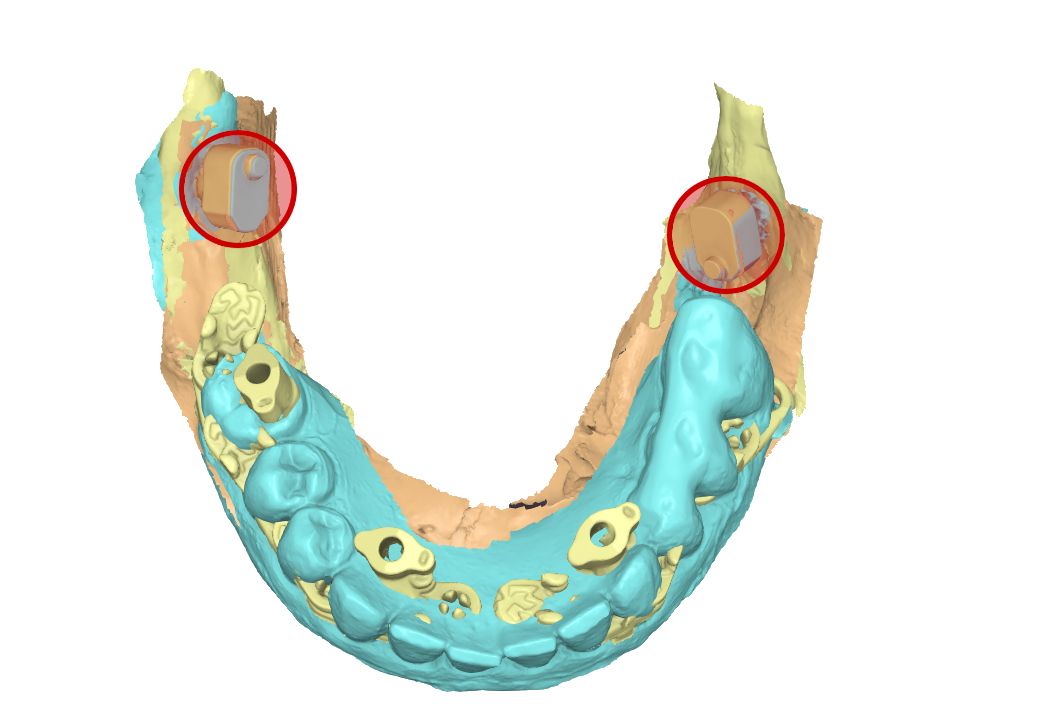

file .stl della sovrapposizione delle tre scansioni

Fig. 8. (a) file .stl della sovrapposizione delle tre scansioni, in evidenza gli ScanSke

Arcate scansionate all’interno dell’articolatore digitale

Fig. 8. (b) Arcate scansionate all’interno dell’articolatore digitale, in evidenza gli ScanSke.

Prospettiva frontale della protesi progettata

Fig. 9. (a) Prospettiva frontale della protesi progettata in base all’occlusione abituale della paziente

Prospettiva dall’alto della protesi inferiore

Fig. 9. (b) Prospettiva dall’alto della protesi inferiore, in evidenza gli Scan Ske.

Prospettiva laterale sinistra della protesi in occlusione

Fig. 9. (c) Prospettiva laterale sinistra della protesi in occlusione, in evidenza gli ScanSke.